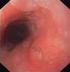

3 1. Epidemiologie, etiologie en vroege detectie oesofaguscarcinoom en Alarmsymptomen, zoals passagestoornissen, vermagering, ernstig braken, hematemesis en/of melena, anemie met tegelijkertijd reflux- of dyspeptische klachten vormen een indicatie voor een endoscopie. Voor het besluit om een endoscopie te laten verrichten speelt leeftijd een beperkte rol. 2. Diagnostiek en stadiëring oesofaguscarcinoom Nadat bij een patiënt de diagnose oesofaguscarcinoom is gesteld, dient eerst de operabiliteit van de patiënt te worden vastgesteld. Alleen indien de patiënt in staat lijkt een operatie te ondergaan, is het noodzakelijk het TNM-stadium vast te stellen. Hierbij staat het T-stadium voor ingroei in de wand van de oesofagus, het N-stadium voor de aanwezigheid van lymfkliermetastasen en het M-stadium voor afstandsmetastasen. Conclusies Niveau 1 Voor de vaststelling van de T-status van een oesofaguscarcinoom is endoscopische ultrasonografie (EUS) superieur gebleken aan andere diagnostische modaliteiten. Niveau 1 Voor de bepaling van lymfkliermetastasen van een oesofaguscarcinoom, zowel locoregionaal als ook op afstand (met name truncaal) is EUS superieur aan andere diagnostische modaliteiten. Hierbij worden suspecte klieren gepuncteerd indien de status van de desbetreffende lymfklieren voor de beleidsbepaling relevant is. Niveau 1 FDG-PET kan de selectie van patiënten met een T3-oesofaguscarcinoom voor een in opzet curatieve benadering verbeteren. Niveau 1 Voor evaluatie van cervicale lymfkliermetastasen is uitwendige echografie het meest geschikt, waarbij voor maligniteit verdachte klieren worden gepuncteerd. Niveau 2 CT is het meest geschikt om metastasen op afstand of in andere orgaansystemen vast te stellen. Niveau 2 Schematische classificatie van bronchoscopische bevindingen aangevuld met brushcytologie van voor maligniteit verdachte gebieden van het slijmvlies van de luchtwegen heeft een hoge accuracy. en Na vaststelling van een oesofaguscarcinoom met endoscopie en histologische bevestiging door de patholoog, dienen de volgende onderzoeken te worden verricht: CT van de thorax-apertuur tot en met de bovenbuik om de aanwezigheid van mediastinale en/of truncale lymfkliermetastasen, als ook mogelijke metastasen in longen, lever, bijnieren of skelet vast te stellen. Hierbij dient zowel gering oraal contrast ter markering van het oesofaguslumen als intraveneus contrast te worden toegepast. De coupedikte dient kleiner of gelijk te zijn aan 5 mm. Echografie van de hals om cervicale lymfkliermetastasen te bepalen. 3

4 FDG-PET bij T3-oesofaguscarcinomen kan worden overwogen om eventuele metastasen op afstand vast te stellen. Endoscopische ultrasound om de uitbreiding van de laesie in de diepte en mogelijke ingroei in omgevende structuren (bijvoorbeeld aorta) (T-status) en de aanwezigheid van vergrote mediastinale en/of truncale lymfklieren te bepalen (N- en M-status). Suspecte cervicale, mediastinale en truncale klieren dienen onder beeldvorming (endoscopische) ultrasound) cytologisch te worden gepuncteerd indien de status van de desbetreffende lymfklieren voor beleidsbepaling relevant is. Bronchoscopie, inclusief brushcytologie van suspecte gebieden, is onderdeel van de stadiëring van oesofaguscarcinomen op of craniaal van het niveau van de carina. Algoritme Diagnostiek oesofaguscarcinoom Stap 1: Diagnose Gastroscopie + biopten Stap 2: Bepalen operabiliteit Criteria: leeftijd, comobiditeit, etc. Stap 3a: Bepalen resectabiliteit CT thorax en abdomen Echo van hals Stap 3b: Bepalen resectabiliteit Endoscopische ultrasonografie (EUS) +/- Fine Needle Aspiration (FNA) Stap 3c: Bepalen resectabiliteit Facultatief: FDG-PET Bronchoscopie Laparoscopie 3. Beleid a. Premaligne afwijkingen en kleine tumoren (T1) Gezien de zeldzaamheid hiervan wordt voor vroegafwijkingen in plaveiselepitheel van de oesofagus verwezen naar de volledige richtlijn. In het navolgende worden vroegafwijkingen bij een barrett-oesofagus besproken. 4

5 Diagnostiek en Bij patiënten met een vroeg-neoplastische afwijking gelden de volgende aanbevelingen in de endoscopische work-up voor eventuele endoscopische therapie: Hogeresolutie-endoscopie is geïndiceerd bij patiënten met een neoplastische afwijking van de oesofagus waarbij endoscopische therapie wordt overwogen. Bij afwijkingen in plaveiselepitheel wordt daarnaast chromoscopie met lugolkleuring aanbevolen. Geadviseerd wordt biopten te nemen uit alle zichtbare mucosale onregelmatigheden en at random uit vier kwadranten voor elke centimeter barrett-oesofagus, te beginnen 1 cm boven de bovenrand van de maagplooien en doorlopend tot aan de overgang van cilindrisch naar plaveiselepitheel. Disseminatieonderzoek Bij alle patiënten met een neoplastische afwijking in de oesofagus bij wie endoscopische therapie wordt overwogen, dient endoscopische ultrasound te worden verricht om diepte-infiltratie van de afwijking en verdachte lokale lymfklieren uit te sluiten. Endoscopische behandeling van patiënten met hooggradige dysplasie of vroegcarcinoom bij een barrett-oesofagus Conclusies Voor geselecteerde patiënten met hooggradige dysplasie en/of vroegcarcinoom bij een barrett-oesofagus lijkt de endoscopische behandeling gelijkwaardig aan chirurgie wat betreft effectiviteit maar geeft deze minder complicaties (< 5%). Niveau 2 Bij ulcererende afwijkingen in de oesofagus is de kans op submucosale ingroei > 95% en is EMR gecontra-indiceerd. Niveau 2 Afwijkingen van 2 cm in maximale diameter en/of de helft van de circumferentie kunnen en bloc worden verwijderd; grotere afwijkingen vereisen piece-meal-resectie, waardoor een hogere kans bestaat op acute complicaties (bloeding, perforatie), stenosering en lokale recidieven. Voor patiënten met hooggradige dysplasie en/of een oppervlakkig vroegcarcinoom is primaire behandeling met fotodynamische therapie effectief gebleken. Na endoscopische behandeling wordt bij ongeveer 30% van de initieel succesvol behandelde patiënten een metachrone afwijking vastgesteld in de resterende barrett-oesofagus. 5